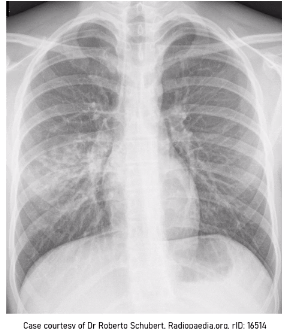

what is this?

costophrenic angle

what is this ?

cardio-phrenic angle